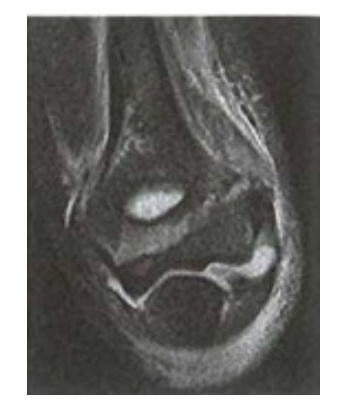

Trên phim XQ thường đôi khi không đánh giá được mức độ gãy và nguy cơ di lệch của mảnh vỡ lồi cầu ngoài, đặc biệt ở trẻ nhỏ tuổi (3-4 tuổi), Chụp MRI với lát cắt 1,5mm- 2mm, ngoài đánh giá được mức độ gãy và nguy cơ di lệch, còn cho phép phát hiện các thương tổn khác của khớp.

Hình ảnh MRI khớp khuỷu trong gãy LCN xương cánh tay trẻ em